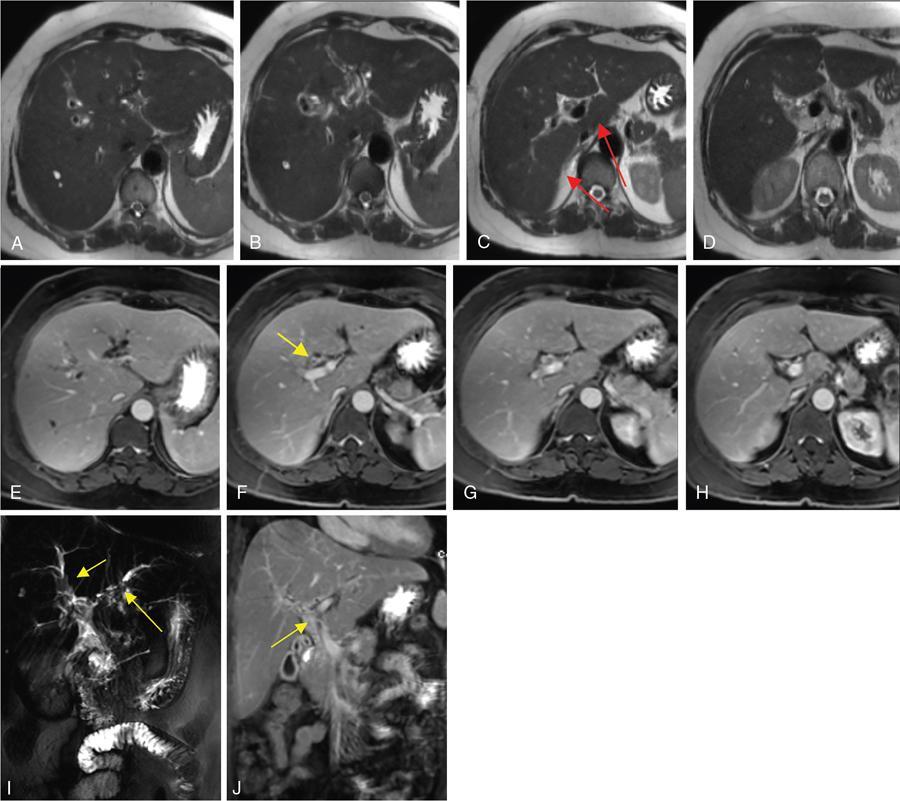

Ritu K. Kashikar, Shrinivas B. Desai, Chandresh Karnavat, Nilesh Doctor The biliary tract is subject to a variety of abnormalities. The spectrum includes benign diseases of autoimmune, infective, ischaemic, infiltrative aetiologies and malignant disorder, which most importantly represents cholangiocarcinoma. Imaging in particular magnetic resonance cholangiopancreatography (MRCP) plays a vital role in diagnosis and follow-up of these disorders. Multidetector computed tomography (MDCT) and magnetic resonance imaging (MRI) are also crucial in preoperative staging of biliary malignancies and making decisions regarding resectability and extent of resection. This chapter focuses on important benign and malignant disorders of the biliary tree and imaging features that aid in differentiation of various entities. A variety of disorders affect the biliary tree. Most biliary disorders manifest as biliary dilatation. The various causes are listed in Table 9.15.1. Imaging plays an important role in identification of aetiology based on pattern of involvement in association with clinical picture. USG is often the first investigation in a patient with jaundice. USG is excellent at showing biliary dilatation. It may be useless in assessing level of obstruction and biliary stones. Changes in liver morphology, development of cirrhosis is accurately done on USG. Early changes in conditions like primary sclerosing cholangitis (PSC), presence of intrahepatic ductal strictures, thickening of common bile duct (CBD) are, however, not confidently seen and need imaging modalities like MRCP and computed tomography (CT). Staging of hilar cancers is also best done on CT or MRI with contrast. Contrast-enhanced CT is extremely accurate in staging hilar cancers. It is a preferred modality to access radial spread of the disease and vascular involvement. Subtle changes of PSC and autoimmune cholangitis may however be missed and MRCP is preferred in these conditions. The protocol for evaluating biliary disease is standard plain scan followed by early, late arterial, portal venous and parenchymal phases similar to that obtained for focal liver lesions. Delayed phase images should be obtained for hilar malignancies, which often show delayed enhancement. MRCP with or without contrast is the modality of choice in diagnosing and characterizing biliary diseases. Owing to its noninvasive nature, it has replaced endoscopic retrograde cholangiopancreatography (ERCP) in the initial evaluation and follow-up of a variety of biliary pathologies. Absence of radiation exposure makes it suitable to obtain follow-ups in patients requiring serial scanning. The ability to diagnose abnormalities of both intra- and extrahepatic biliary tree, level of obstruction, longitudinal and radial spread of neoplastic process make it an ideal modality. MRCP protocol includes T2 weighted single-shot fast spin-echo, T1 weighted in phase and opposed phase gradient echo, diffusion-weighted imaging, T2-weighted fat-suppressed fast spin-echo in axial and coronal. A pre contrast three-dimensional T1-weighted fat-suppressed spoiled gradient-echo image is obtained in addition to 3-D MRCP. Postcontrast protocol includes dynamic three-dimensional T1-weighted fat-suppressed spoiled gradient-echo (in arterial, late arterial and portal venous, parenchymal and delayed phases). Since the advent and widespread use of MRCP, the utility of ERCP in diagnosing biliary pathologies has significantly reduced. ERCP is primarily used when stenting or other procedures need to be performed in the same setting. Although an invasive procedure with postprocedural risk of pancreatitis ERCP allows excellent depiction of biliary changes in conditions like PSC, recurrent pyogenic cholangitis (RPC) and IgG4-related disorders. Endoscopic USG (EUS) is an excellent modality in diagnosing lower bile duct pathologies and also has the added advantage of obtaining a biopsy in the same setting. EUS is less invasive than ERCP and overall safer. PSC is a premalignant cholestatic liver disorder characterized by bile duct strictures secondary to bile duct inflammation and fibrosis. Cirrhosis of liver can develop secondary to this condition and patients are at a high risk for biliary and colonic cancers. PSC is a relatively rare disease, with an incidence of less than 50 per 100,000 patients though it varies in various location. It is diagnosed in young patients aged 30–40 years and is twice as common in men than in women. Similar to other autoimmune diseases, genetic susceptibility is likely to be instrumental in the development of PSC after exposure to a trigger. There is also a strong association between PSC and human leukocyte antigens (HLAs). Environmental factors such as childhood microbial exposure also play an important role in disease pathogenesis. A strong association of PSC with inflammatory bowel disease (IBD) is seen. There is a 100-fold increased risk of developing PSC among siblings. PSC can be asymptomatic but may present with cholestatic symptoms such as jaundice, pruritus, fatigue and right upper quadrant pain, steatorrhoea and episodes of acute bacterial cholangitis. There is marked elevation of alkaline phosphatase (ALP). A twofold to threefold increase in serum alanine and aspartate aminotransferase (AST) can be seen. Elevated bilirubin is usually seen in advanced disease, malignancy or those with choledocholithiasis. Various serum antibodies can also be elevated in PSC. These have been enlisted in Table 9.15.2. On liver biopsy, classic pathologic features of periductal concentric fibrosis or ‘onion skin’, around the affected ducts can be seen. This is however not a pathognomonic finding and is seen in less than 40% of biopsy specimens. Therefore, biopsy is not routinely used as a diagnostic tool for PSC and is reserved primarily for disease staging. MRI with MRCP best depicts the biliary changes in PSC and is the modality of choice. While CT and USG may show biliary dilatation and changes of cirrhosis in advanced cases, they fail to show early changes (Table 9.15.3). USG is an effective modality for the visualization of dilatation and diffuse wall thickening of the extrahepatic bile duct. Other feature seen on USG is bright echogenic portal triad. However, the role of USG in the diagnosis of early PSC is limited owing to suboptimal assessment of the intrahepatic biliary ducts. Features of advanced disease such as heterogeneous coarse echogenicity can be readily detected with USG. The major benefit of performing US is to guide liver biopsy. Also, liver stiffness as assessed by transient elastography correlated well with the degree of liver fibrosis in PSC patients. CT can demonstrate some findings suggestive of sclerosing cholangitis such as focal, discontinuous, often peripheral intrahepatic biliary duct dilatation and thickening with enhancement of the bile ducts owing to inflammation. CT is effective in helping exclude other causes that can result in biliary stasis and dilatation such as hepatic and pancreatic lesions. CT is also excellent in diagnosing tumours, which may sometimes have similar presentation. Concomitant changes of IBD, if present, can be seen. However, CT is limited in assessment of biliary strictures and visualization of disease involving small peripheral bile duct, especially in the early stages of the disease. CT shows changes of cirrhosis in liver and assessing changes of portal hypertension. MRCP is diagnostic imaging modality of choice in the workup of patients with suspected PSC, as recommended by both the AASLD and EASL guidelines. MRCP has high diagnostic sensitivity (86%) and specificity (94%) for the detection of PSC (Table 9.15.3). Multifocal short segmental strictures in the intra- or extrahepatic biliary tree with intervening normal or dilated duct leading to beaded appearance are seen in early disease. The location in strictures is usually at the biliary bifurcation and are disproportionate to upstream dilatation. Advanced cases show pruning of peripheral biliary radicals secondary to advancing fibrosis obliterating the smaller ducts. An obtuse angle between the central and peripheral ducts is suggestive of PSC. Diverticula and webs also can be seen, though not pathognomonic (Table 9.15.4) (Figs. 9.15.1–9.15.3). Strictures of the CBD of less than 1.5 mm and of left, right or common hepatic duct (CHD) of less than 1 mm are defined as dominant stricture. A dominant stricture is associated with worse prognosis in part due to development of cholangiocarcinoma. MRCP plays an important role in raising the suspicion and guiding treatment. A dominant stricture may be confused with hilar cholangiocarcinoma on imaging and it is often impossible to distinguish the two based on imaging alone (Table 9.15.4) (Fig. 9.15.4). Changes in liver morphology are seen in the form of distortion. The classical change described in PSC includes hypertrophy of the caudate lobe and atrophy of the left lateral and right posterior segments of the liver. Hypertrophy of caudate lobe is more frequent in PSC than cirrhosis from other aetiologies. Other parenchymal changes include heterogeneity of liver, periportal cuffing, peripheral inflammation, cirrhosis and features of portal hypertension. Hyperintensity of the liver parenchyma in PSC on nonenhanced T1-weighted images has been reported. Wedge-shaped peripheral atrophic areas of confluent hepatic fibrosis are seen as high T2-weighted signal intensity. Periportal oedema is visualized as high signal intensity in periportal region on T2-weighted. Increased heterogeneous peripheral enhancement of the liver parenchyma can be seen and is likely due to the altered blood supply in those areas in response to parenchymal inflammation (Table 9.15.4) (Figs. 9.15.5 and 9.15.6). MR elastography is the most accurate noninvasive method for the diagnosis and staging of liver fibrosis and could potentially replace liver biopsy. It is predictive of progression to decompensated liver disease. However, lack of wide availability are still major limiting factors. MR elastography is not influenced by obesity or anatomical conditions (e.g. narrow intercostal spaces and ascites) and the sample size of the liver is significantly higher and hence has several advantages over ultrasound elastography (Table 9.15.5). Besides these features, enlarged reactive abdominal lymph nodes, commonly periportal and portocaval lymph nodes, are commonly diagnosed in PSC and should not be misdiagnosed as a lymphoproliferative disorder or metastatic disease. Though ERCP has higher diagnostic accuracy in detecting PSC, its role is limited to intervention required in PSC due to its invasive nature and potential complications. Also it is recommended that MRCP be performed prior to ERCP as a preprocedural MRCP can provide a road map to the endoscopist. Small duct PSC is a variant PSC syndrome with biochemical markers and histologic features suggestive of PSC with normal cholangiography. It is associated with better prognosis. Approximately one-fourth of patients’ progress to classic PSC in an average of 8 years. Bile duct calculi are a common complication of PSC. Pigmented bile duct stones are common owing to biliary stasis. Both intrahepatic and extrahepatic biliary stones can be found. However, the presence of biliary tree stones is not an essential diagnostic feature. Soft calcific foci within dilated bile ducts can be seen on US and CT images. MRI with MRCP is the imaging modality of choice to detect bile duct stones and appear as focal areas of signal-intensity-void filling defects on T2-weighted images. Usually isointense at T1-weighted imaging but frequently are hyperintense. The presence of biliary strictures puts these patients at risk of bacterial cholangitis in PSC patients. The classic Charcot triad of fever, abdominal pain and jaundice can be seen. Early enhancement of the biliary wall due to the biliary duct inflammation is a common finding with peribiliary reactive hepatic parenchymal changes. Cholangitic abscesses may sometimes be seen. PSC patients are at high risk of developing cholangiocarcinoma during the disease course with and a total risk of 10%–15%. Approximately 30% of all cholangiocarcinomas are detected within the first year of establishing a diagnosis of PSC and so it is important to be suspicious even at the time of PSC diagnosis and to survey for early detection. Rapid clinical deterioration, worsening of jaundice, pruritus, weight loss along with elevation in serum bilirubin and ALP should raise suspicion of PSC. It may be difficult to distinguish benign from malignant strictures. Progressive bile duct wall thickening, irregularity, enhancement, new onset biliary dilatation, dominant stricture or development of focal strictures with dilatation and ipsilateral atrophy are indeterminate features that may raise possibility if occult cholangiocarcinomas. Perivascular thickening, vascular involvement or occlusion are features favouring malignancy. Definite diagnosis is however often not possible on imaging alone and a brush biopsy should be taken in patients with new onset clinical symptoms, elevated tumour makers or above-mentioned indeterminate imaging features (Table 9.15.7). The most common subtype of cholangiocarcinoma in PSC patients is periductal type, characterized by long segment irregular wall thickening along the bile duct with no identifiable mass. The lesion is hypointense on T1W1 images and hyperintense on T2W1 images showing progressive enhancement on contrast study. The tumour could be at the bifurcation and can cause abrupt cut-off, commonly presenting as Klatskin tumour (Fig. 9.15.7). Combined UC and PSC is associated with a higher risk for colorectal carcinoma than UC alone. PSC is considered as an independent risk factor for development of colorectal carcinoma in patients with UC. Malignancy tends to involve the right colon or more proximal parts of the colon. Clinical presentation and history in patients with ascending cholangitis differ from those with PSC. Fever, pain and jaundice dominate the presentation in patients with ascending cholangitis while patients with PSC may be asymptomatic. The typical findings of PSC including biliary duct stenosis, beading or pruning are not typical findings in the newly diagnosed cases of acute ascending cholangitis. Wedge-shaped peripheral and/or intrahepatic peribiliary foci of increased T2 signal around the dilated radicals with arterial and/or delayed parenchymal enhancement has been described in ascending cholangitis. Patients with RPC present with recurrent episodes of abdominal pain, fever, jaundice and chills. These features differ from those in patients with PSC. Hepatolithiasis with pigmented stones in the biliary tree and upstream and downstream duct dilatation are typical imaging features in RPC (Table 9.15.8). Ischaemic cholangiopathy is a form of biliary injury resulting from decreased arterial supply. History of liver transplantation is the key in diagnosing ischaemic cholangiopathy. Biliary strictures in AIDS cholangiopathy are indistinguishable from PSC. However, the combination of papillary stenosis and intrahepatic ductal strictures appears relatively unique to AIDS cholangiopathy; this combination is not found in PSC. Clinical history may help to distinguish one from the other. Effective medical therapy for PSC is lacking. Oral ursodiol (ursodeoxycholic acid) is one of the main treatment options of cholestatic diseases though does not prevent disease progression. Azathioprine and steroids are recommended for use in patients with AIH as well as those with AIH–PSC overlap syndrome. Vedolizumab is a gut-specific monoclonal antibody that has been tried but the clinical utility in PSC–IBD patients remains under investigation. Dilatation of biliary strictures, stenting, lithotripsy and stone extraction can be done with the aid of ERCP and percutaneous transhepatic cholangiography (PTC). The only definitive cure of PSC is, however, liver transplantation. Treatment of complications like choledocholithiasis stone removal can be accomplished by using standard endoscopic techniques with or without sphincterotomy, with balloon or basket extraction for extrahepatic biliary stones. For bacterial cholangitis, immediate administration of broad-spectrum antibiotic therapy is recommended and in abscess formation percutaneous drainage with intravenous antibiotic therapy shows favourable outcome compared with surgical drainage. Incidence is 20%–25%. Diagnosis of recurrent PSC requires careful evaluation, as there are other causes of biliary changes after liver transplant with similar features. Nonanastomotic biliary strictures imply the diagnosis of recurrent PSC only if they occur more than 90 days after transplant. Characteristic multifocal strictures and segmental dilatations of biliary ducts are suggestive findings. MRCP is the initial modality. RPC is characterized by a triad of recurrent biliary sepsis, inflammatory biliary strictures and intrahepatic stones. Fifty per cent of patients may have acute pancreatitis. Oriental cholangiohepatitis, primary hepatolithiasis, Hong Kong disease and oriental infestational cholangitis. Prevalence in the third and fourth decades of life with equal frequency among men and women peak. Southeast Asia predominantly in rural population and in lower socioeconomic groups. Gut-derived organisms lead to sepsis, which initiates a cascade of events, which leads to a chronic, progressive and recurrent inflammatory process in cholangioles. Associations with Clonorchis sinensis, Opisthorchis species, Fasciola hepatica and Ascaris lumbricoides infestations have been suggested. Common organisms cultured from bile include Escherichia coli, Klebsiella, Pseudomonas and Proteus species and anaerobes. Structural biliary abnormalities may develop before stones are demonstrable. Strictures may be seen at cholangiography without stones and vice versa. Entrapped stones cause stasis, sepsis, scarring and stricturing with the increasing lithogenicity (Table 9.15.9). Typically present with abdominal pain, fever and jaundice (the Charcot triad) and commonly provide history of repeated episodes. Routine investigations may demonstrate leukocytosis, deranged liver enzymes with obstructive pattern. Elevated cholestatic markers (bilirubin, ALP and gamma GT) and deranged LFTs can be seen. Serum inflammatory markers can be elevated. Additional tests aiding in differential diagnosis include autoantibodies, ANCA, CA19-9 and serologic tests for Echinococcus. Histology is usually not required. It shows fibrous mural thickening of bile ducts and periductal tissue, as well as acute and chronic inflammatory changes. The imaging features include changes in bile ducts, development of calculi and changes in the parenchyma. The disease affects intrahepatic ducts more than the CHD and CBD. Disproportional dilatation of central intrahepatic ducts and extrahepatic bile ducts is seen with nondilated or minimally dilated peripheral ducts, leading to abrupt tapering of bile ducts. All segments of biliary tree may be involved, but the lateral segment of the left lobe is most often and extensively involved most likely because left hepatic ducts come off at a more acute angle compared with the right hepatic ducts, thus predisposing to stasis and stricture formation (Table 9.15.10). Hepatolithiasis is common in patients with RPC. Stones are composed mainly of bile pigments with variable calcification. There may be single or multiple stones scattered in the intra- or extrahepatic ducts or both. The dilatation of the extrahepatic duct is generally not related to the location of the stone. Ducts both proximal and distal to the stone are dilated. Parenchymal atrophy most commonly involves the left lateral and right posterior segments while hypertrophy of the caudate and right lobe is seen. USG shows dilatation of the central intrahepatic and extrahepatic ducts, with relative sparing of the peripheral biliary tree. Hepatolithiasis can be seen in 90% of cases. The echogenicity and acoustic shadowing of calculi may vary depending on extent of calcification. There is often associated periportal echogenicity. Ultrasound may be useful in performing image-guided percutaneous drainage of abscesses or biopsy of suspicious lesions. Limitations include inability to detect subtle intrahepatic ductal dilatation and heavy stone burden obscuring evaluation of underlying hepatic parenchyma. Contrast-enhanced CT is increasingly being used as first line of imaging. It allows for detection of characteristic disproportionate dilatation of the extrahepatic and central intrahepatic ducts. Contrast-enhanced CT also allows for detection of bile duct wall enhancement, suggestive of acute cholangitis. Ninety per cent stones are hyperdense to liver parenchyma on nonenhanced scan. Extent of calcification in calculi may vary. Parenchymal atrophy affects left lateral segment most frequently, followed by right posterior segments. Eventually, changes of cirrhosis can be seen. Heterogeneous appearance of liver parenchyma with segmental steatosis and altered enhancement can be seen particularly during acute attack. Pneumobilia is not infrequent and can usually be attributed to recent procedures or surgeries like bilioenteric anastomosis. It may, however, be seen in patients without history of prior interventions due to recent passage of stone through the ampulla or less commonly cholangitis related to gas forming organisms (Fig. 9.15.8). Subtle intrahepatic ductal strictures and noncalcified stones may be missed on CT. MRCP allows visualization of both intra- and extraductal disease and can reveal complete extent, severity and complications of the disease. Even noncalcified calculi which may be missed on CT or sonography, are seen as intraductal filling defects on heavily T2-weighted images and may appear hyperintense to the liver on T1-weighted images. MRI demonstrates central and extrahepatic duct dilatation with decreased arborization and abrupt tapering of peripheral ducts. MRI particularly MRCP sequences accurately depicts stenotic segments and delineates the entire biliary tree, including the proximal part of the stricture, without risk of aggravating biliary sepsis. Even short segment duct strictures <1 cm are easily seen on MRCP (Figs. 9.15.8 and 9.15.9). Parenchymal abnormalities like hepatic atrophy, whether diffuse or segmental, and altered signal can be accurately diagnosed. Mass lesions and hepatic abscesses, if present, are also well delineated. The characteristic finding of disproportionate dilatation of the ducts, with multiple intraductal calculi are well demonstrated. There may also be intrahepatic strictures, with abrupt tapering of the peripheral ducts as well as decreased arborization of the biliary tree (arrowhead appearance). It allows for better spatial resolution, thus permitting better evaluation of the smaller peripheral ducts. The main limitation of ERCP is its invasive nature, with complications such as ERCP-associated pancreatitis. Heterogeneous parenchymal enhancement, wall thickening and periductal enhancement are seen in acute cholangitis. Abscess formation is encountered in up to 20% of RPC patients who undergo cross-sectional imaging. The abscesses can occur in both the affected and unaffected portions of the liver but most commonly seen in the right lobe. Sonography guided aspiration can be done when diagnosis is doubtful. Intrahepatic bile lakes are not infrequent and may or may not communicate with the biliary tree. On USG bilomas appear anechoic and are usually hypodense on CT with or without calculi. Leakage of bile from a severely dilated obstructed duct may lead to formation of extrahepatic biloma. Cholangiocarcinoma is the most feared complication and may be seen in up to 5% of patients. Segments with high stone burden or those with atrophy are more prone to developing cholangiocarcinoma. Clinical and laboratory indicators for development of cholangiocarcinoma in patients with PSC include increase in jaundice without associated cholangitis, sudden weight loss, significant elevation of ALP and rising tumour markers. Peripheral cholangiocarcinoma manifests as expansion of the affected segment. Hypoattenuating mass with showing peripheral enhancement causing narrowing of the portal vein may raise suspicion of malignancy. Portal vein thrombosis has also been reported but is rare. Recurrent biliary sepsis may lead to periductal inflammation and portal thrombophlebitis. Portal thrombosis can lead to lobar atrophy with compensatory hypertrophy of the uninvolved lobe. Higher incidence of hepatocellular carcinoma (HCC) is reported in patients with RPC due to development of cirrhosis in severe cases. Management should comprise antibiotic treatment, clearance of stones, maintenance of biliary drainage and long-term follow-ups. ERCP allows for therapeutic procedures such as stone removal and stenting of strictures. Destroyed liver segments, those with multiple abscesses and patients with secondary cholangiocarcinoma are candidates or surgery. Stone extraction can also be done surgically with the aid of basket, forceps, balloon catheter or flexible choledochoscope. Transduodenal sphincteroplasty and hepaticojejunostomy are commonly performed drainage procedures. Indications for transplantation include extensive bilobar hepatolithiasis, cirrhosis and liver failure. IgG4 cholangiopathy is a cholangitis characterized by elevated serum IgG4 and infiltration of the bile duct wall with IgG4 positive plasma cells leading to storiform fibrosis and obliterative phlebitis with resultant bile duct wall thickening. This condition shows good response to steroids. Frequent association with IgG4-related autoimmune pancreatitis is seen. IgG4 sclerosing cholangitis (IgG4-SC) has a threefold to fivefold higher prevalence in men than women. It usually presents in the fifth and sixth decades of life. Incidence of this disease is approximated to be around 0.28–1.08/100,000. Autoimmunity has been considered as the most probable pathogenesis of IgG4-related disease (IgG4-RD). Several HLA association have identified as determinants of disease susceptibility. The major histologic features associated with IgG4-RD have been well described and include the steps. Chronic or recurrent cholangitis is the most common presentation and seen in up to 75% cases. Other symptoms seen are fever, pruritus, pain and weight loss. Biliary involvement may be detected incidentally in patients being scanned for symptoms related to involvement of other organs such as pancreas. One-quarter of patients with IgG4-SC may be asymptomatic. Serum liver tests show a cholestatic pattern with often marked elevation of ALP and γ-GT and only mildly increased ALT and AST. Serum bilirubin may be increased. Tumour marker CA 19-9 is not able to distinguish pancreatobiliary malignancies from IgG4-SC since levels of >1000 IU/mL (ULN = 37 IU/mL) may be observed in IgG4-SC. IgG4 levels are elevated (>140 mg/dL) in up to 75%–80% of affected patients. A cut-off level of 207 mg/dL might be useful for completely distinguishing IgG4-SC from cholangiocarcinoma. Elevated bile fluid IgG4 has a high sensitivity and specificity of 100% at a cut-off level of 113 mg/dL and seen only in cases of IgG4-RD, neither PSC nor cholangiocarcinoma. Approximately 40% of patients have peripheral blood eosinophilia, often accompanied by asthma and atopy. Patients may show hypergammaglobulinemia, elevated serum IgE. Several diagnostic criteria have been developed to aid in the diagnosis of IgG4-SC. The most widely used is the HISORt (Histology, Imaging, Serology, other Organ involvement and Response to therapy) criteria of the Mayo Clinic. This tool was initially used to diagnose AIP but can be adapted to diagnose IgG4-SC by Ghazele et al. (Tables 9.15.13 and 9.15.14). It is often the initial investigation and may be normal early in the course of the disease. Circumferential thickening of the bile ducts with biliary dilatation is seen later in the disease. US also helps in the identification of associated findings affecting other organs. However, US has low sensitivity in detecting the disease and is suboptimal for assessing the extent of the disease. Contrast-enhanced CT though not the investigation of choice shows bile duct wall thickening with proximal mild dilatation. The intrapancreatic bile duct segment is more commonly involved. The most important finding is circumferential symmetric wall thickening of the bile ducts, frequently involving the extrahepatic segments, with smooth outer and inner margins. In addition, the thickened segment shows progressive homogeneous contrast enhancement, further increasing in the delayed phase. As opposed to malignancies, wall thickening or stricturing of bile ducts in IgG4-RD is not associated with proportionate proximal biliary dilatation (Figs. 9.15.10 and 9.15.11). In addition to the above findings, imaging findings of IgG4 disease affecting other organs, that is, gallbladder wall thickening, changes of autoimmune pancreatitis, retroperitoneal fibrosis and kidney findings can be seen. MRI is the investigation of choice. MRI findings are similar to CT findings and include circular and symmetric long segmental thickening of the bile duct wall with smooth outer and inner margins. Bile duct wall thickening can be seen in nonstenotic areas as well The other findings are the visibility of patent bile duct in the strictures, disproportionate proximal dilatation, hyperenhancement during the late arterial phase, homogeneous hyperenhancement during the delayed phase, concurrent gallbladder wall thickening and no vascular invasion (Table 9.15.15).